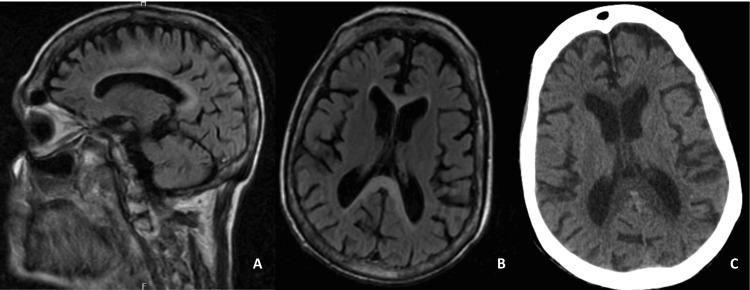

Marchiafava-Bignami disease (MBD) is a rare condition characterized by demyelination and necrosis of the corpus callosum, most commonly associated with chronic alcohol consumption. However, it can also occur in non-alcoholic patients and may present secondary to other underlying conditions. We report a case of a 52-year-old male with no history of alcohol use or significant comorbidities, presenting with impaired consciousness and severe malnutrition. Neuroimaging findings confirmed MBD, and further investigation revealed an underlying oropharyngeal malignancy that likely precipitated the disease through feeding difficulties and nutritional deficits. Analytical findings revealed severe metabolic derangements, including hypoalbuminemia and vitamin deficiencies. Despite aggressive treatment, the patient succumbed to his condition. This case highlights the importance of considering MBD in the differential diagnosis of neurological dysfunction in patients with significant malnutrition and emphasizes the need for a thorough investigation into underlying causes, including malignancy.

马尔恰法瓦-比尼亚米病(MBD)是一种罕见疾病,其特征为胼胝体脱髓鞘和坏死,最常与长期饮酒相关。然而,它也可发生于非酒精性患者,并且可能继发于其他潜在疾病。我们报告一例52岁男性病例,该患者无饮酒史或重大合并症,表现为意识障碍和严重营养不良。神经影像学检查结果确诊为MBD,进一步检查发现潜在的口咽恶性肿瘤,该肿瘤可能通过进食困难和营养缺乏引发了该病。分析结果显示严重的代谢紊乱,包括低白蛋白血症和维生素缺乏。尽管进行了积极治疗,患者仍因病情过重死亡。该病例突出了在严重营养不良患者的神经功能障碍鉴别诊断中考虑MBD的重要性,并强调了对包括恶性肿瘤在内的潜在病因进行全面调查的必要性。